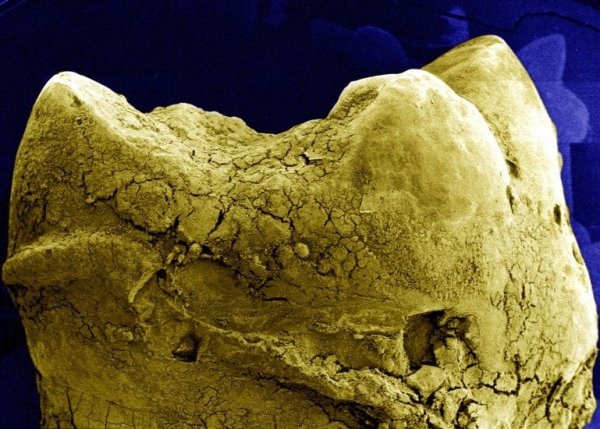

1. A fog felszíne fogkővel

Kezdjük talán a nagyobb léptékű dolgokkal. Ez a kép az emberi fog felszínéről nagyszerűen szemlélteti, hogy miért is hasznos a mindennapos fogápolás. Amint az a pásztázó mikroszkóppal készült felvételen remekül látszik, a fog felülete egyáltalán nem egyenletes, így aztán a kórokozók is sokkal könnyebben tapadnak meg rajta, mint azt gondolnánk. Én ezt a fotót kötelezően megmutatnám minden nagycsoportos óvodásnak. Szerintem igazán hatásos.

Credit David Gregory&Debbie Marshall, Wellcome Images